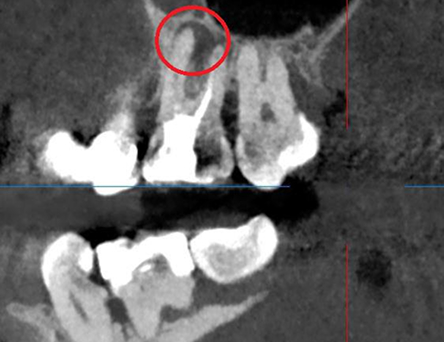

Перелечивание зуба с кистой под микроскопом

Проблема: У пациента отек щеки, боли самопроизвольные, усиливающиеся при приеме пищи, неудачное первичное лечение зуба (старыми методами).

Лечение: Проведено эндодонтическое перелечивание зуба под дентальным микроскопом, что позволило точно выявить анатомические особенности корневых каналов и устранить последствия ранее некачественного лечения. После купирования воспалительного процесса (киста) каналы герметично запломбированы. Коронковая часть зуба восстановлена для сохранения функции и герметичности до этапа постоянного протезирования.

Результат: После проведённого лечения болевые ощущения полностью устранены, отёк щеки исчез, воспалительный процесс купирован. Зуб сохранён, восстановлена его функция. Установлена коронка, что позволило полностью восстановить анатомическую форму и жевательную эффективность зуба.